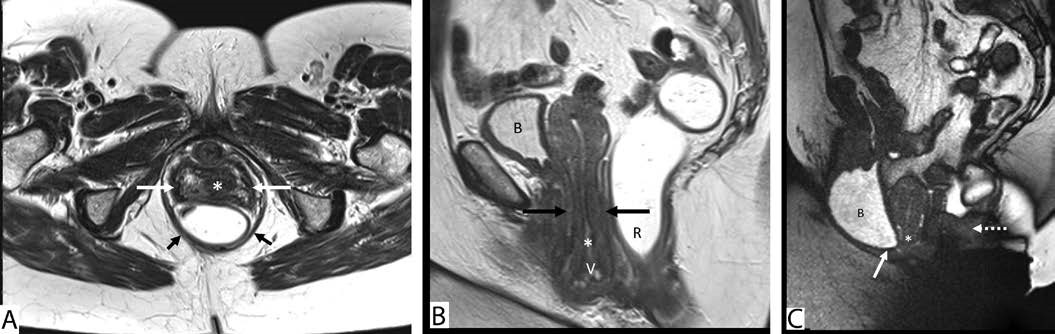

Some institutions use vaginal contrast on MRD in female patients to assist in detection of vaginal vault prolapse, and authors have reported using volumes ranging from 5 to 60 mL,[16],[17],[18],[19] but there is no convincing evidence in the literature to support routine use of vaginal contrast during MRD. Given its high spatial and contrast resolution, MRI allows direct visualization of soft tissue structures in the pelvis such as the anterior and posterior vaginal walls and vaginal apex (Figs. 2 and 3), precluding the need for routine use of vaginal contrast[20] and avoiding the added burden on patient privacy and discomfort.[3],[4] Furthermore, if the vaginal contrast is not expelled during the examination, it could conceivably mask vaginal prolapse (descent of vaginal apex below the pubococcygeal line (PCL)) or prolapse in other compartments. Thus, there was consensus among the experts against the routine use of vaginal contrast for MRD.

Posterior vaginal wall prolapse is often secondary to rectocele, which is defined as anterior bulging or ballooning of the rectum into the rectovaginal septum. Clinically, rectoceles may cause weakening and lengthening of the vaginal wall and manifest as a posterior vaginal bulge and/ or defecatory dysfunction. However, both rectoceles and cul-de-sac hernias can result in vaginal bulge on physical examination.[28] Furthermore, sometimes rectoceles apparent on clinical examination may not manifest on imaging with MRD. Experts discussed the relatively poor correlation between physical examination and imaging for the detection of rectocele. Decisions regarding appropriateness of surgical repair of rectoceles apparent on imaging and not on physical examination (or vice versa) are often multifactorial based on the patient- and clinicianrelated factors,[30],[31] and discussion of appropriate indications is outside the scope of these guidelines. Nonetheless, the consortium experts agreed that rectoceles should be described when seen on MRD and should be measured in maximal anterior-posterior dimension during defecation. A vertical drawn up from the anorectal junction during defecation extrapolates the normal location of the rectal wall at rest. A horizontal line drawn from this vertical line to the most maximally displaced portion of the anterior rectal wall should be considered the anterior-posterior dimension of the rectocele (Fig. 2C; see Video 2 http:// links.lww.com/DCR/B652) . Furthermore, any resultant deformity of the vaginal wall should be described. Similar to other findings, radiologists should avoid using language that implies severity or grading terminology such as mild/ moderate/severe because the imaging finding may not always correlate with patient symptomatology. Further comment should be made on whether the rectoceles empty with maximum effort or whether they retain contrast. It was noted that contrast retention within a rectocele on MRD does not always correlate with the finding of contrast retention on fluoroscopic defecography, presumably because of differences in consistency between the types of rectal contrast used for fluoroscopy and MRI. When a rectocele does not fully empty, a further comment should be made as to whether the patient can empty fully with digital splinting or manipulation. Furthermore, in patients who have a paradoxical occlusion of the anus or contraction of the puborectalis with defecation, a comment about the timing of the rectocele development in relationship to the timing of the paradoxical contraction of the pelvic floor can provide further insight into the best treatment approach to these patients.